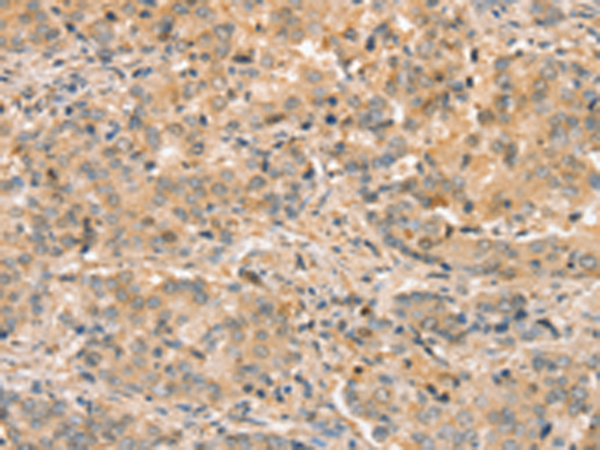

分类: 科研抗体货号: P12199别名: CRT; CT1; CRTR; CTR5; CCDS1应用: IHC反应种属: Human, Mouse, Rat